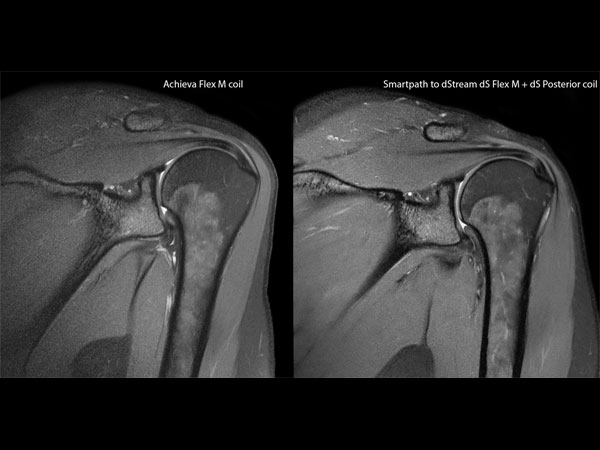

Shoulder imaging with dS Flex coil

Used Solution

• System

• Coil